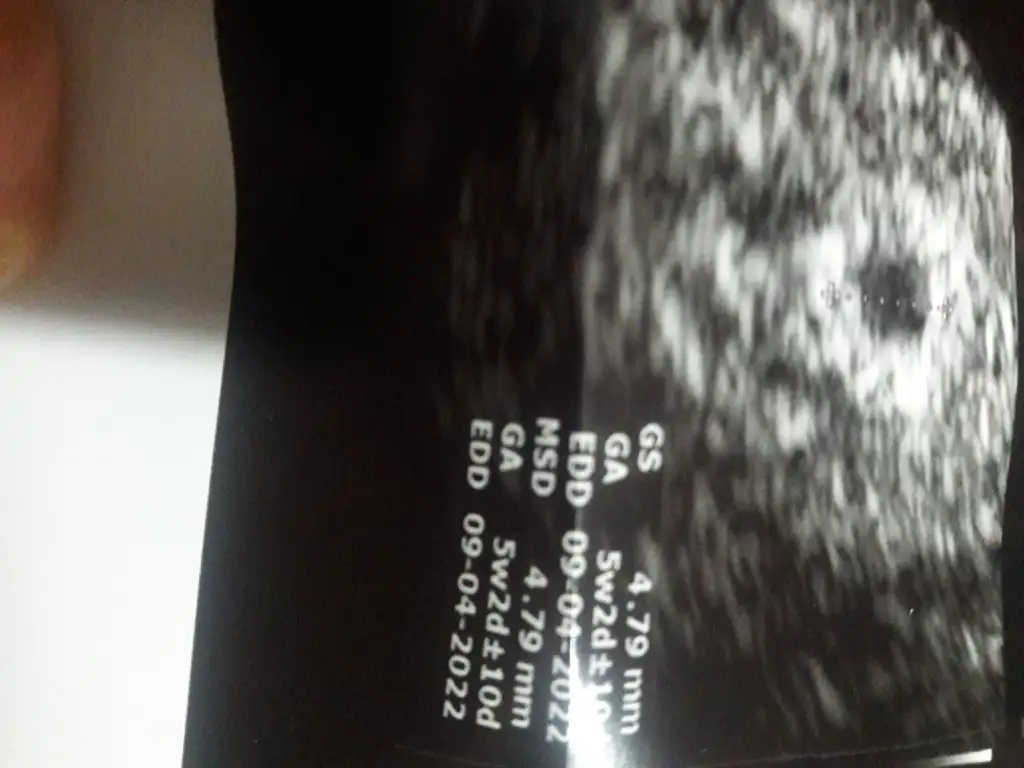

Bende de kese var yolk var fetusta 2.06 diye işaretledi.benimde bende geçici menepoza soktogunda bir kez adet getirici ilaç verdi adetliyken göreyim dedi yani 22haziran benimde son adet tarihim seninle aynı sayılırız bak sana iki tane ultrason kağıdımı aticam 10gun arayla olan

Aynen öyle gelişen bir durum yok bekliyecek bir durumda yok boşu boşuna bekletiyo bir sürüde ilaç kullanıyorum boşu boşuna vücuduma hormon yüklüyorum.10gun önce kesenin içi hiç belli değildi şimdi küçük birşey gördü kesede bozulmada yok bu durumda kestirip atamam dedi biraz daha bekleyelim dedi 27sinde tekrar bakılcak artık bi karar verir yoruldum çok artik😔